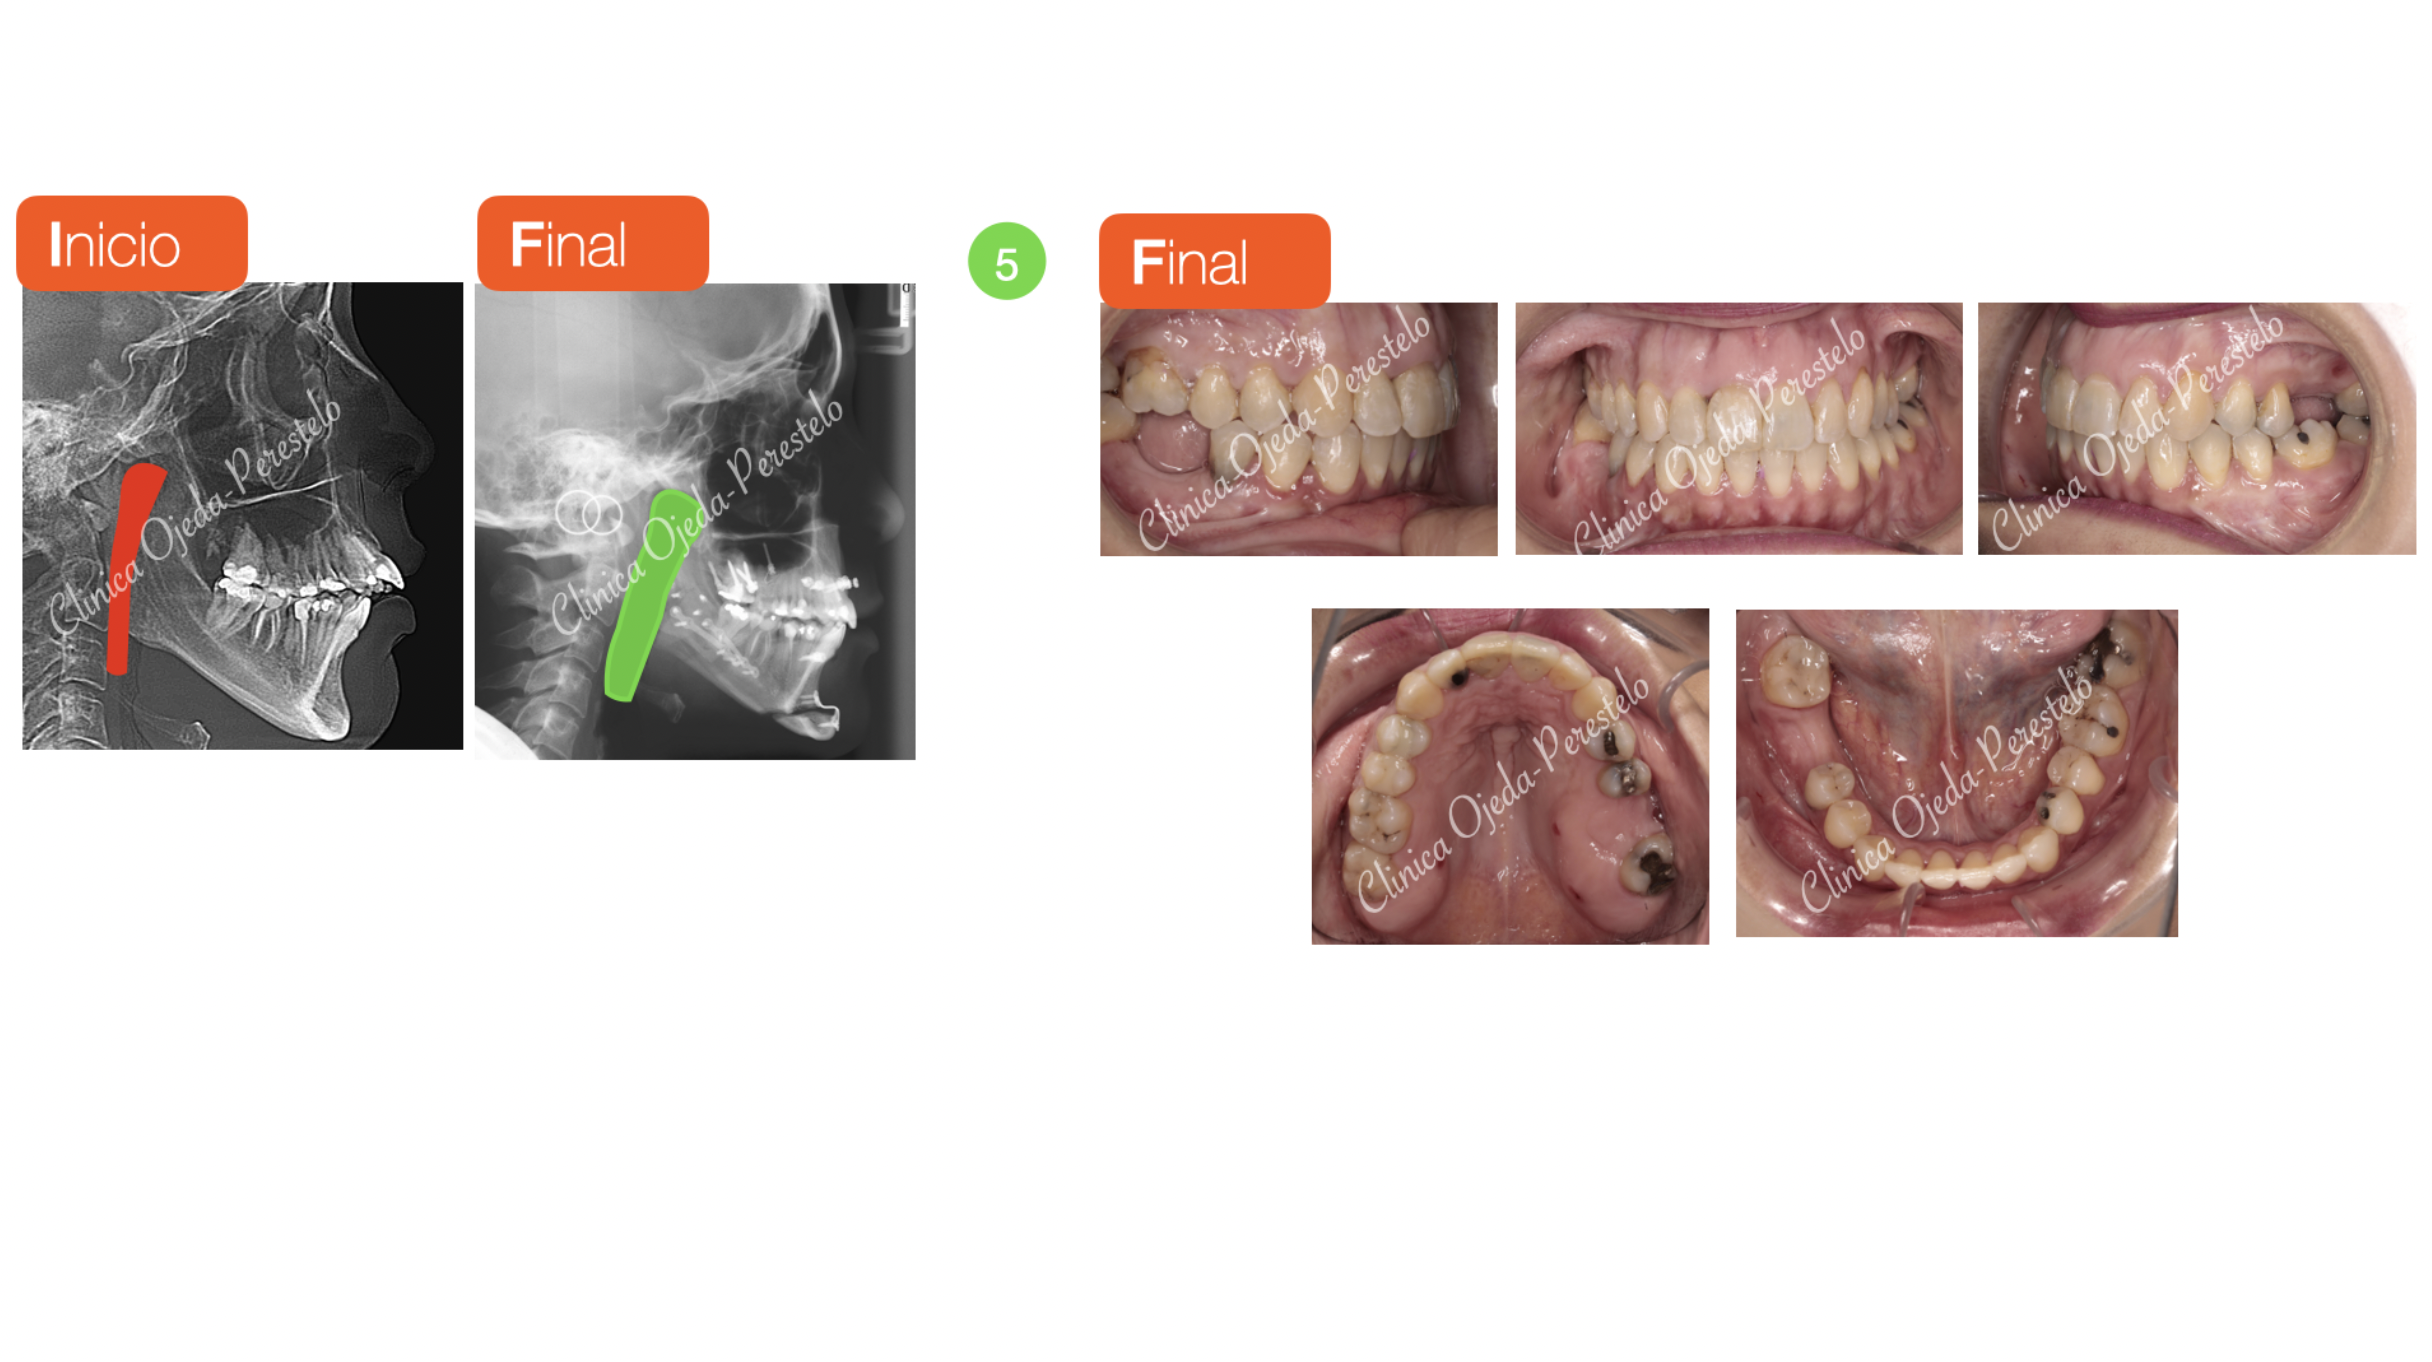

Clase II esquelética con Cirugía de Avance Md

En la actualidad todos aquellos pacientes subsidiarios de Cirugía Ortognática pueden verse beneficiados de realizar un tratamiento ortodóncico-quirúrgico con Alineadores Transparentes. Presentamos la evolución de una paciente tratada con alineadores transparentes y  Cirugía de  avance mandibular en 4 etapas diferenciadas:

Se ha alcanzado el objetivo con 89 alineadores Maxilares y 87 Mandibulares con cambio semanal en 2 años y 9 meses. Quisiéramos destacar la mejoría en la dimensión de Vía Aérea dotándole a la paciente, ahora sí, de un mejor descanso sin ronquidos. En la actualidad la paciente está pendiente de colocarse sus implantes en zona 46-26, así como de injertos en las piezas 22 y 23 para mejorar su recesión.